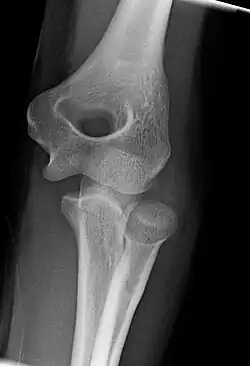

Right: AP X ray of a dislocated right elbow

Fractures

There are three bones at the elbow joint, and any combination of these bones may be involved in a fracture of the elbow. Patients who are able to fully extend their arm at the elbow are unlikely to have a fracture (98% certainty) and an X-ray is not required as long as an olecranon fracture is ruled out.[27] Acute fractures may not be easily visible on X-ray.[28]

Dislocation

Elbow dislocations constitute 10% to 25% of all injuries to the elbow. The elbow is one of the most commonly dislocated joints in the body, with an average annual incidence of acute dislocation of 6 per 100,000 persons.[30] Among injuries to the upper extremity, dislocation of the elbow is second only to a dislocated shoulder. A full dislocation of the elbow will require expert medical attention to re-align, and recovery can take approximately 6 weeks.